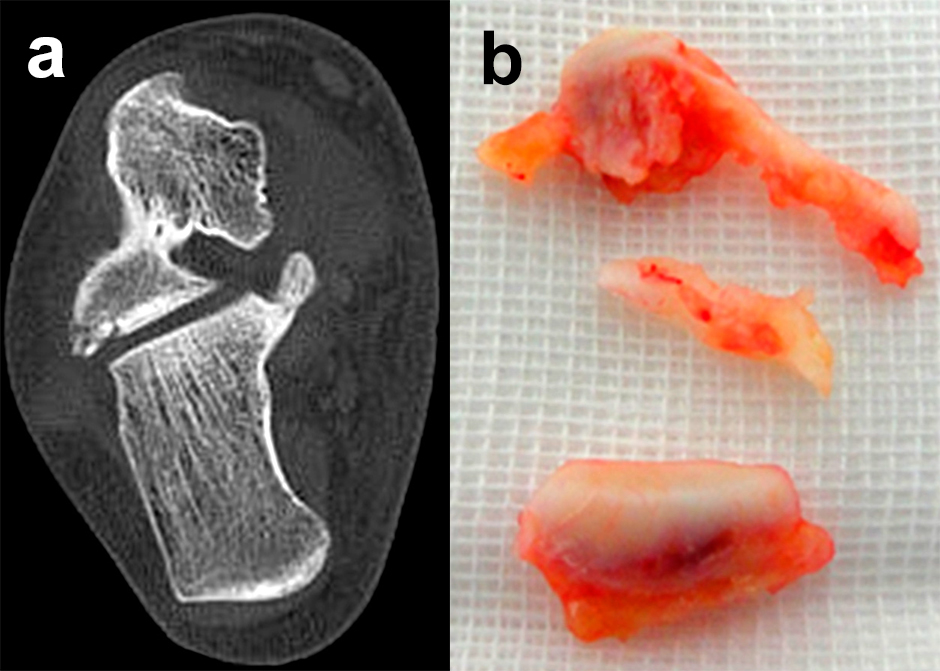

Eine exakte Abgrenzung von Taluskorpus- und Talushalsfrakturen ist allein anhand von Standard-Röntgenaufnahmen nicht sicher möglich. Inokuchi und Mitarbeiter definierten daher Talushalsfrakturen mittels CT, wobei die Frakturlinie distal vor dem Proc. fibularis talis ausläuft 6 (Abb. 1). Es ist anzunehmen, dass sich mit dieser Definition die oben angegebenen Zahlen von den Talushalsfrakturen etwas zu den Taluskorpusfrakturen verschieben, zumal diese mehrheitlich anhand von Röntgenaufnahmen erhoben wurden.

Frakturen des Proc. fibularis tali werden im konventionellen Röntgenbild nicht selten übersehen. Sie entstehen häufig nach schweren Distorsionen bzw. im Rahmen subtalarer Luxationen. Eine CT-Kontrolle nach geschlossener Reposition subtalarer Luxationen ist daher obligat (Ab. 15). Der Proc. fibularis tali ist über den anterolateralen Zugang oder schräg verlaufenden Ducroquet-Ollier-Zugang gut zu erreichen. Die subtalare Arthroskopie über anterolaterale und posterolaterale Portale bietet wie bei intraartikulären Kalkaneusfrakturen die Möglichkeit der exakten Kontrolle der geschlossenen Reposition bei einfachen Frakturformen 35. Nach anatomischer Reposition und temporärer Fixierung mittels 1,0 Kirschnerdraht erfolgt die Osteosynthese mittels Kleinfragmentschrauben (2,7 bzw. 3,5 mm), die unterhalb der Knorpel- Knochengrenze eingebracht werden und für eine ausreichende Stabilität sorgen (Abb. 16). Kleinere, nicht anatomisch refixierbare Fragmente, oder Fragmente mit starker Knorpelkontusion werden vorzugsweise exzidiert (Abb. 17). Gleiches gilt für Frakturen des Proc. posterior tali zur Vermeidung einer posttraumatischen Arthrose 23736.